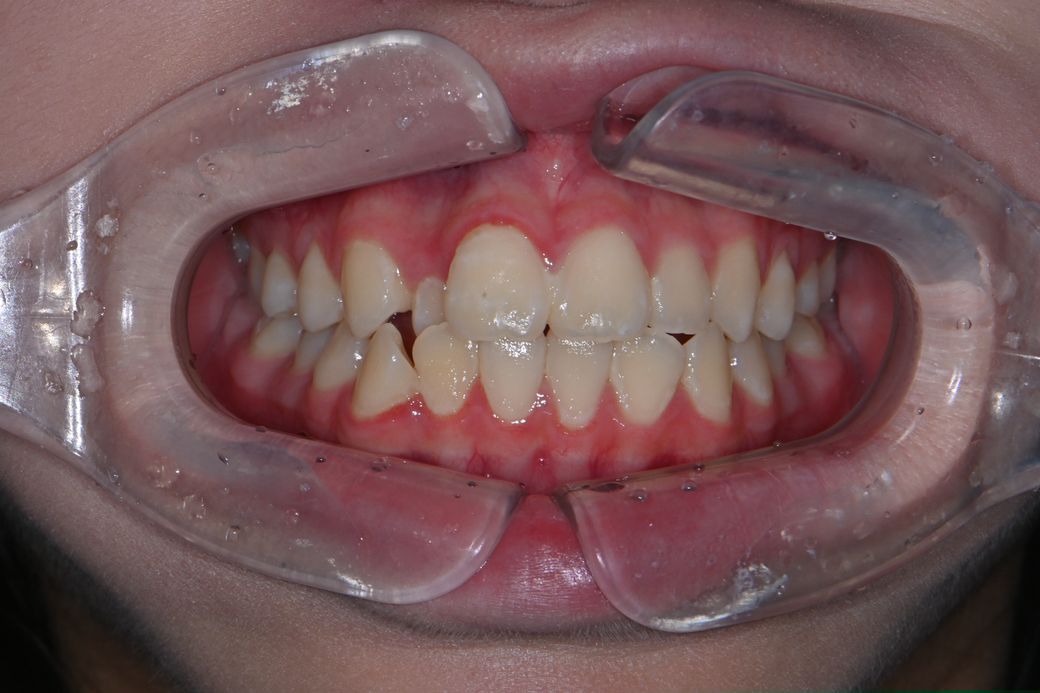

중1 여자 아이 교정진단 부탁드립니다.

앵글씨 몇급인지 궁금합니다.

의사 선생님마다 소견이 다르셔서 혼란 스럽네요.중1 여자 아이구요.시기적으로 지금 교정을 시작하기에 적절한지 궁금합니다.

앵글 2급 부정교합이며, 지금 교정하는 것이 좋을 것으로 보입니다. 더 늦어지면 교정이 까다로워 질 수도 있습니다. 지금 현재도 쉬운 케이스는 아닙니다.

앵글씨 부정교합측면에서 보면 1급인거 같고 치열이 좋지 않아서 중학교 1학년이면 교정을 시작하셔도 괜찮을 시기인거 같습니다.